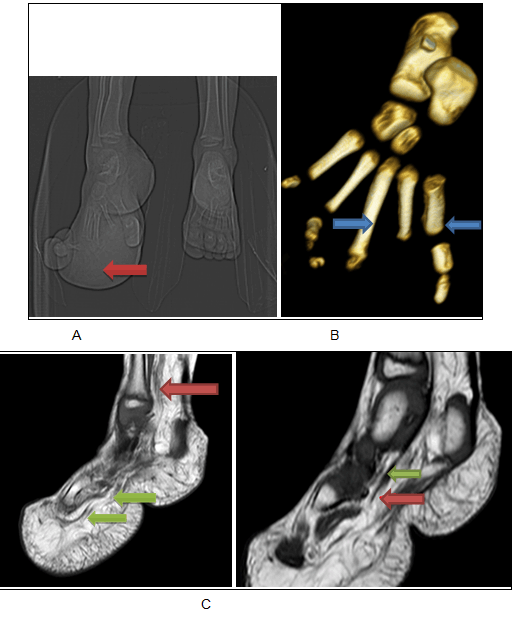

A three-year-old girl was referred to our department for magnetic resonance imaging (MRI) evaluation of local gigantism of the right foot. Parents gave history of enlargement of right foot since birth, particularly the 2nd and 3rd toes for which the patient was operated at one and a half years of age in some remote hospital. There was some cosmetic improvement after the operation. However, operative records were not available at time of presentation. She had been relatively asymptomatic with only mild pain over her sole from plantar keratosis. However, in last six months parents noticed further accelerated overgrowth of her right foot including the adjacent great toe. Physical examination revealed diffuse enlargement of her right foot with exceptionally large first and third toes. Also painless non-compressible soft tissue overgrowths were palpable at the lateral aspect of ankle and plantar aspect of foot. No dilated superficial vein or vascular mark was noticed. Contralateral foot was normal. No other skeletal abnormality was found. Previously, there was plain CT scan done from outside with the patient. Plain CT scan revealed significantly overgrown right foot with overgrowth of both bony and soft tissue compartments. The overgrown soft tissue compartment was predominantly lucent suggestive of fatty nature. Both CT scan and reconstructed 3D bony images revealed enlarged and thickened 1st, 2nd and 3rd metatarsals and residual phalanges with widening of inter-digital gap. Postoperative changes can be appreciated in 2nd and 3rd toes. Magnetic resonance imaging scan of the right lower leg, ankle and foot was performed. There was increased deposition of subcutaneous fat at the lateral and posterior aspects of the ankle, posterior and plantar aspects of the heel, plantar surface of foot with disproportionately enlarged first and residual third toes. The increased fatty overgrowth had the same signal intensity as rest of the normally visualized subcutaneous fat. Streaky T1-hypointense and T2-hypointense signal intensities suggestive of fibrous strands could be observed inside the overgrown subcutaneous fat. The right tibial nerve distal part was fusiform enlarged with abundant lipomatous tissue seen as T1 hyperintense component with suppression on FatSat sequences interspersed among the thickened nerve fascicles (Figure 3). The imaging findings were consistent with macrodystrophia lipomatosa and which was further confirmed on biopsy. Based on clinical history, radiographic evaluation and histopathological examination diagnosis of recurrent macrodystrophia lipomatosa was made. |